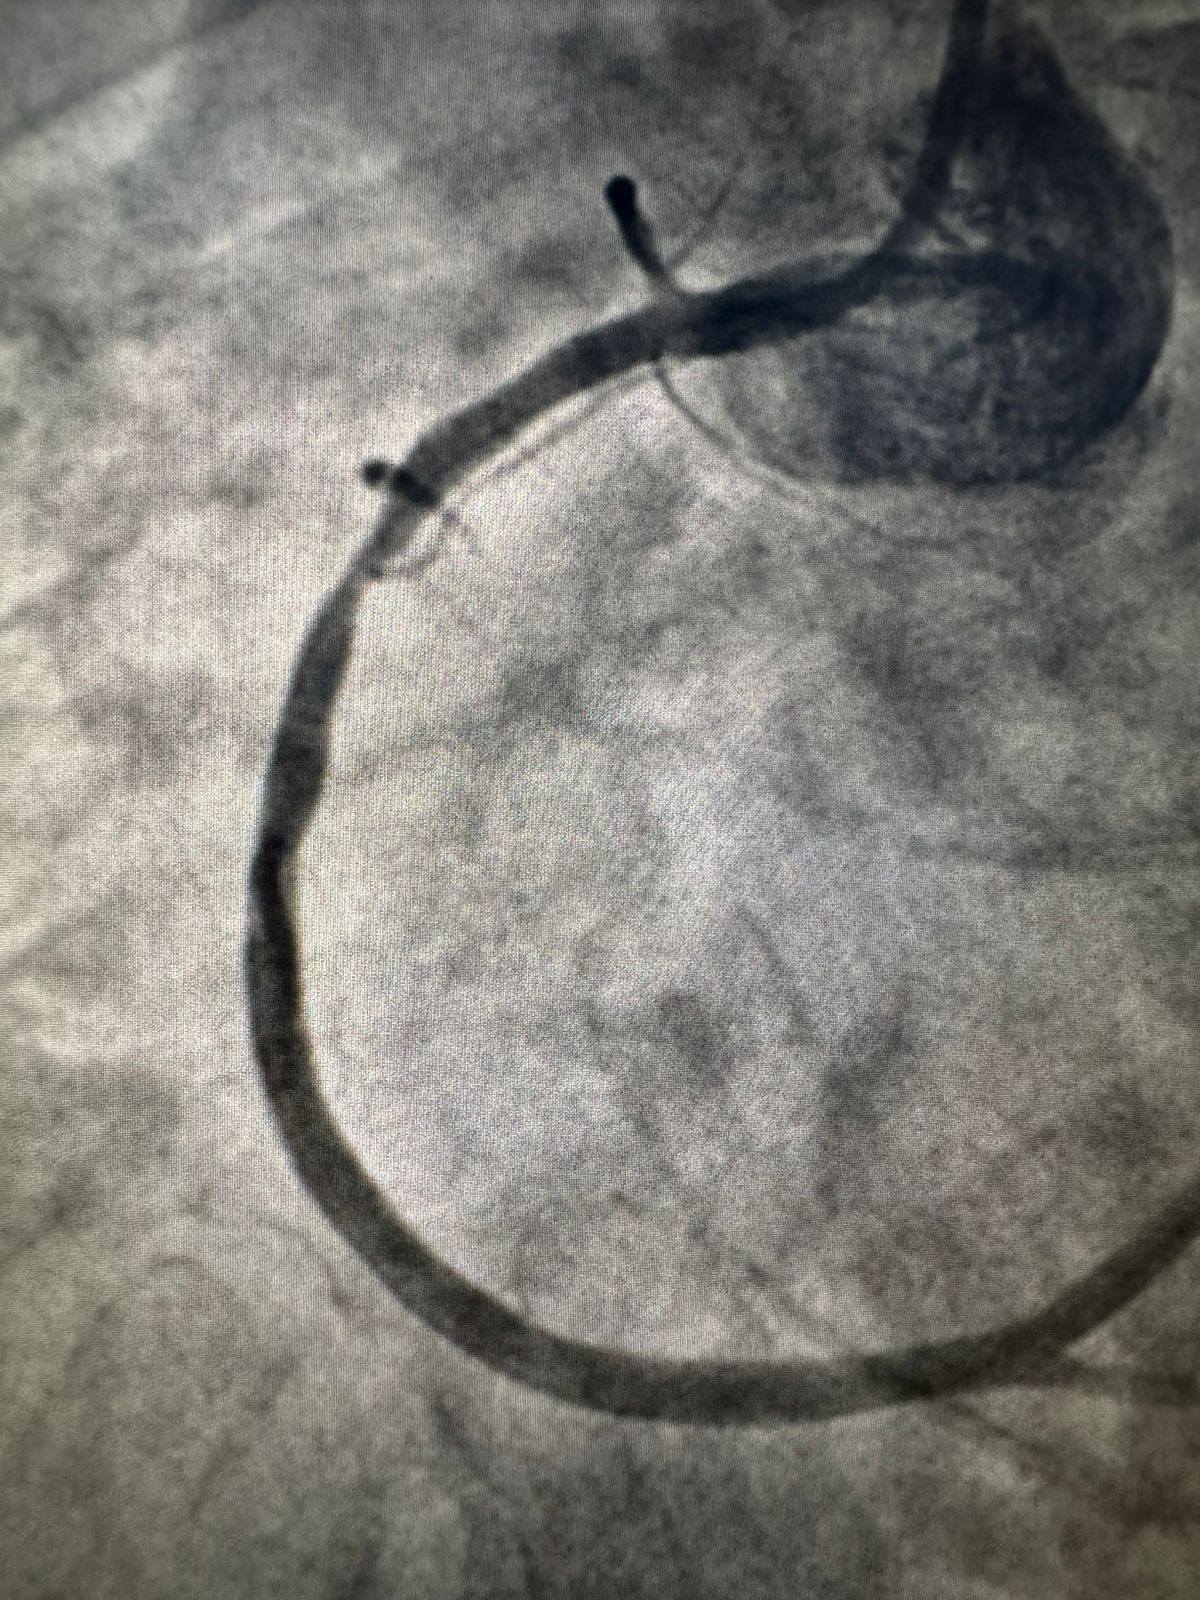

La Tunisie vient d’inscrire son nom dans l’histoire médicale du continent africain. Pour la première fois en Afrique, une endoprothèse coronaire résorbable de troisième génération — le Fantom® Encore — a été implantée avec succès à l’Hôpital universitaire La Rabta de Tunis. Une avancée réalisée au sein du service de cardiologie du professeur Sami Mourali, en collaboration avec des experts internationaux, notamment allemands.

Contrairement aux stents métalliques classiques qui demeurent à vie dans l’artère, le Fantom® Encore est conçu pour se résorber progressivement après avoir accompli sa mission. Cette endoprothèse biorésorbable rouvre les artères coronaires obstruées, maintient leur ouverture le temps nécessaire, puis disparaît naturellement de l’organisme — sans laisser aucun corps étranger permanent.

Cette approche représente un bénéfice considérable pour les patients jeunes, exposés sur le long terme aux complications potentielles des implants permanents. En éliminant le risque lié à la présence durable d’un dispositif étranger, la technologie améliore significativement la qualité du suivi thérapeutique et la liberté de mouvement des parois artérielles.